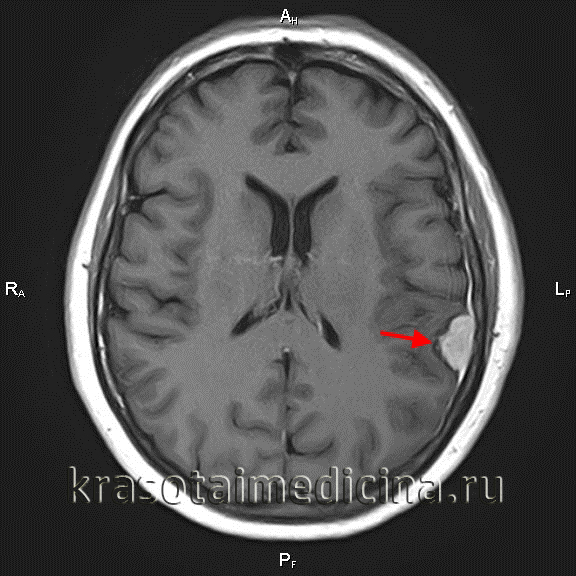

Краниофарингиома.

Гетерогенное образование, растущее в третий желудочек, с крупными кистозными компонентами, имеющими разную интенсивность кистозной жидкости (аксиальный срез) (сверху).

Сагиттальный снимок демонстрирует интраселлярную опухоль, дающую гетерогенный сигнал, и многочисленные кистозные образования, окружающие солидную опухоль (снизу).